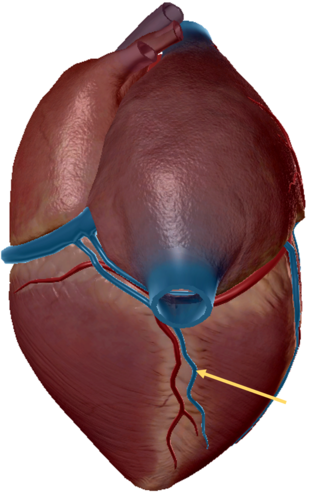

coronary sinus

inferior vena cava

anterior inter ventricular sulcus

middle cardiac vein

coronary sinus